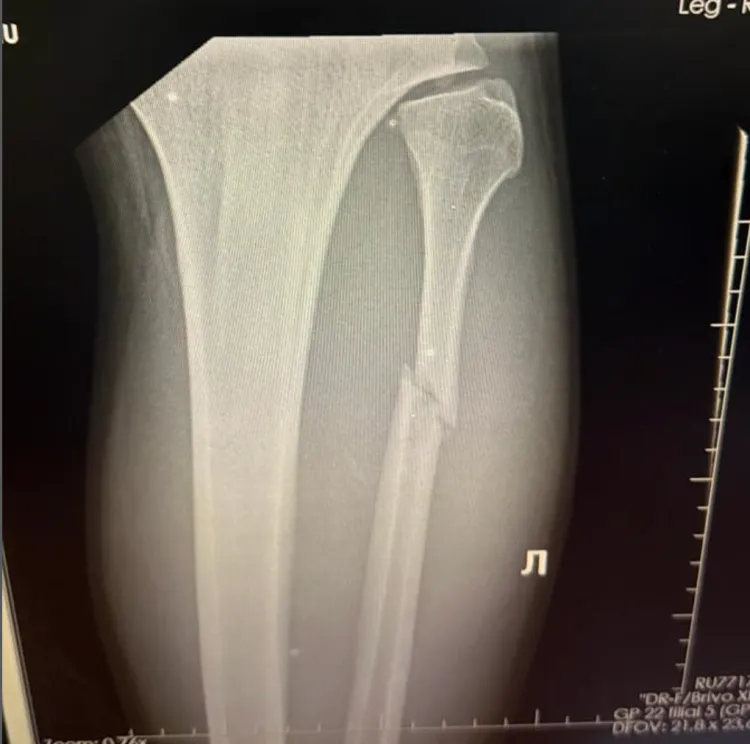

A trip to the doctor confirmed the damage: a cracked fibula. Fortunately, no surgery will be needed, and Walker expects to return to action by February or March 2026.

“The doctor said it’s like five or six weeks for recovery,” Walker said. “I just need to use the cast and not put weight on it. If I do, maybe the bone moves and I’ll need surgery.”